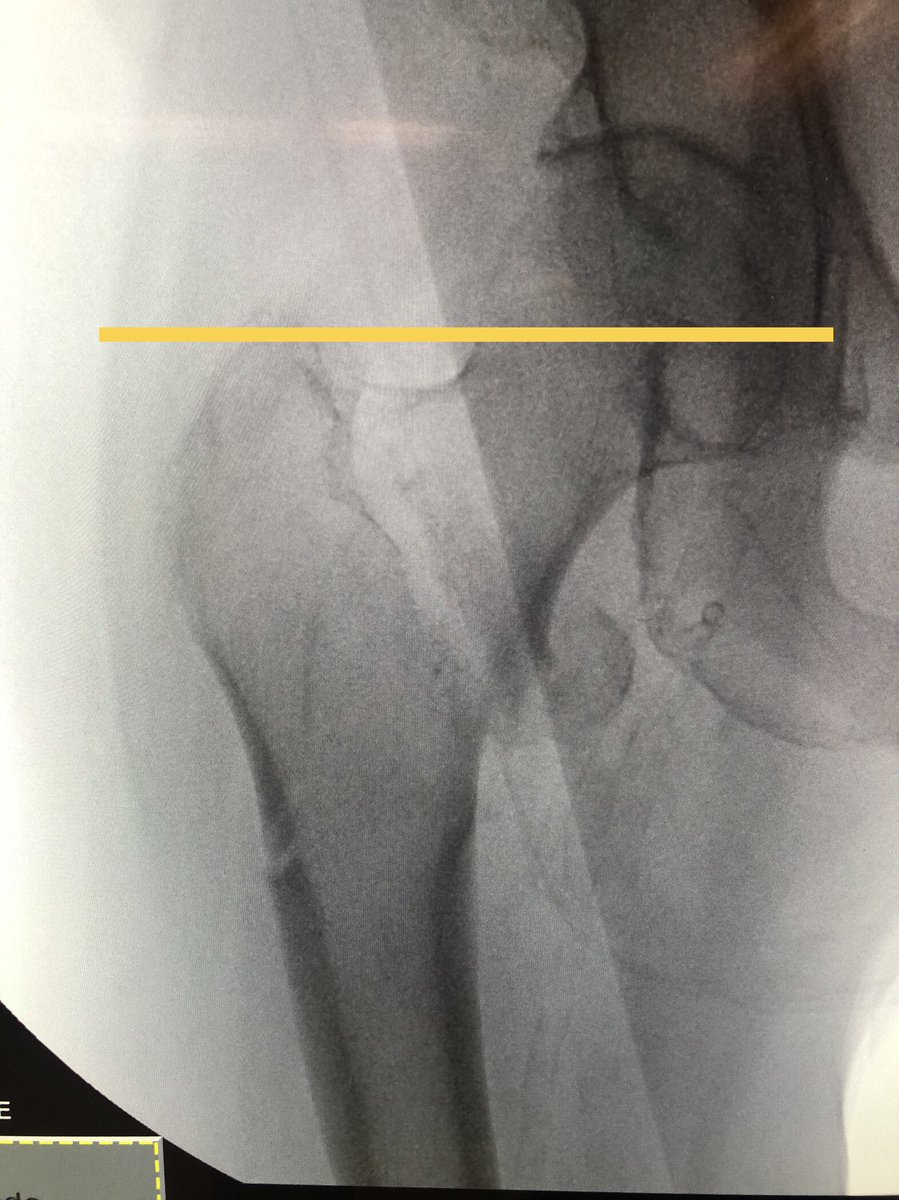

[4/18] The correct amount of traction, if you don’t want to judge by the other side, is usually close when greater trochanter lines up w/center of femoral head (yellow). You can play around with it and see how it looks. Can also always clamp if traction alone isn’t good enough.